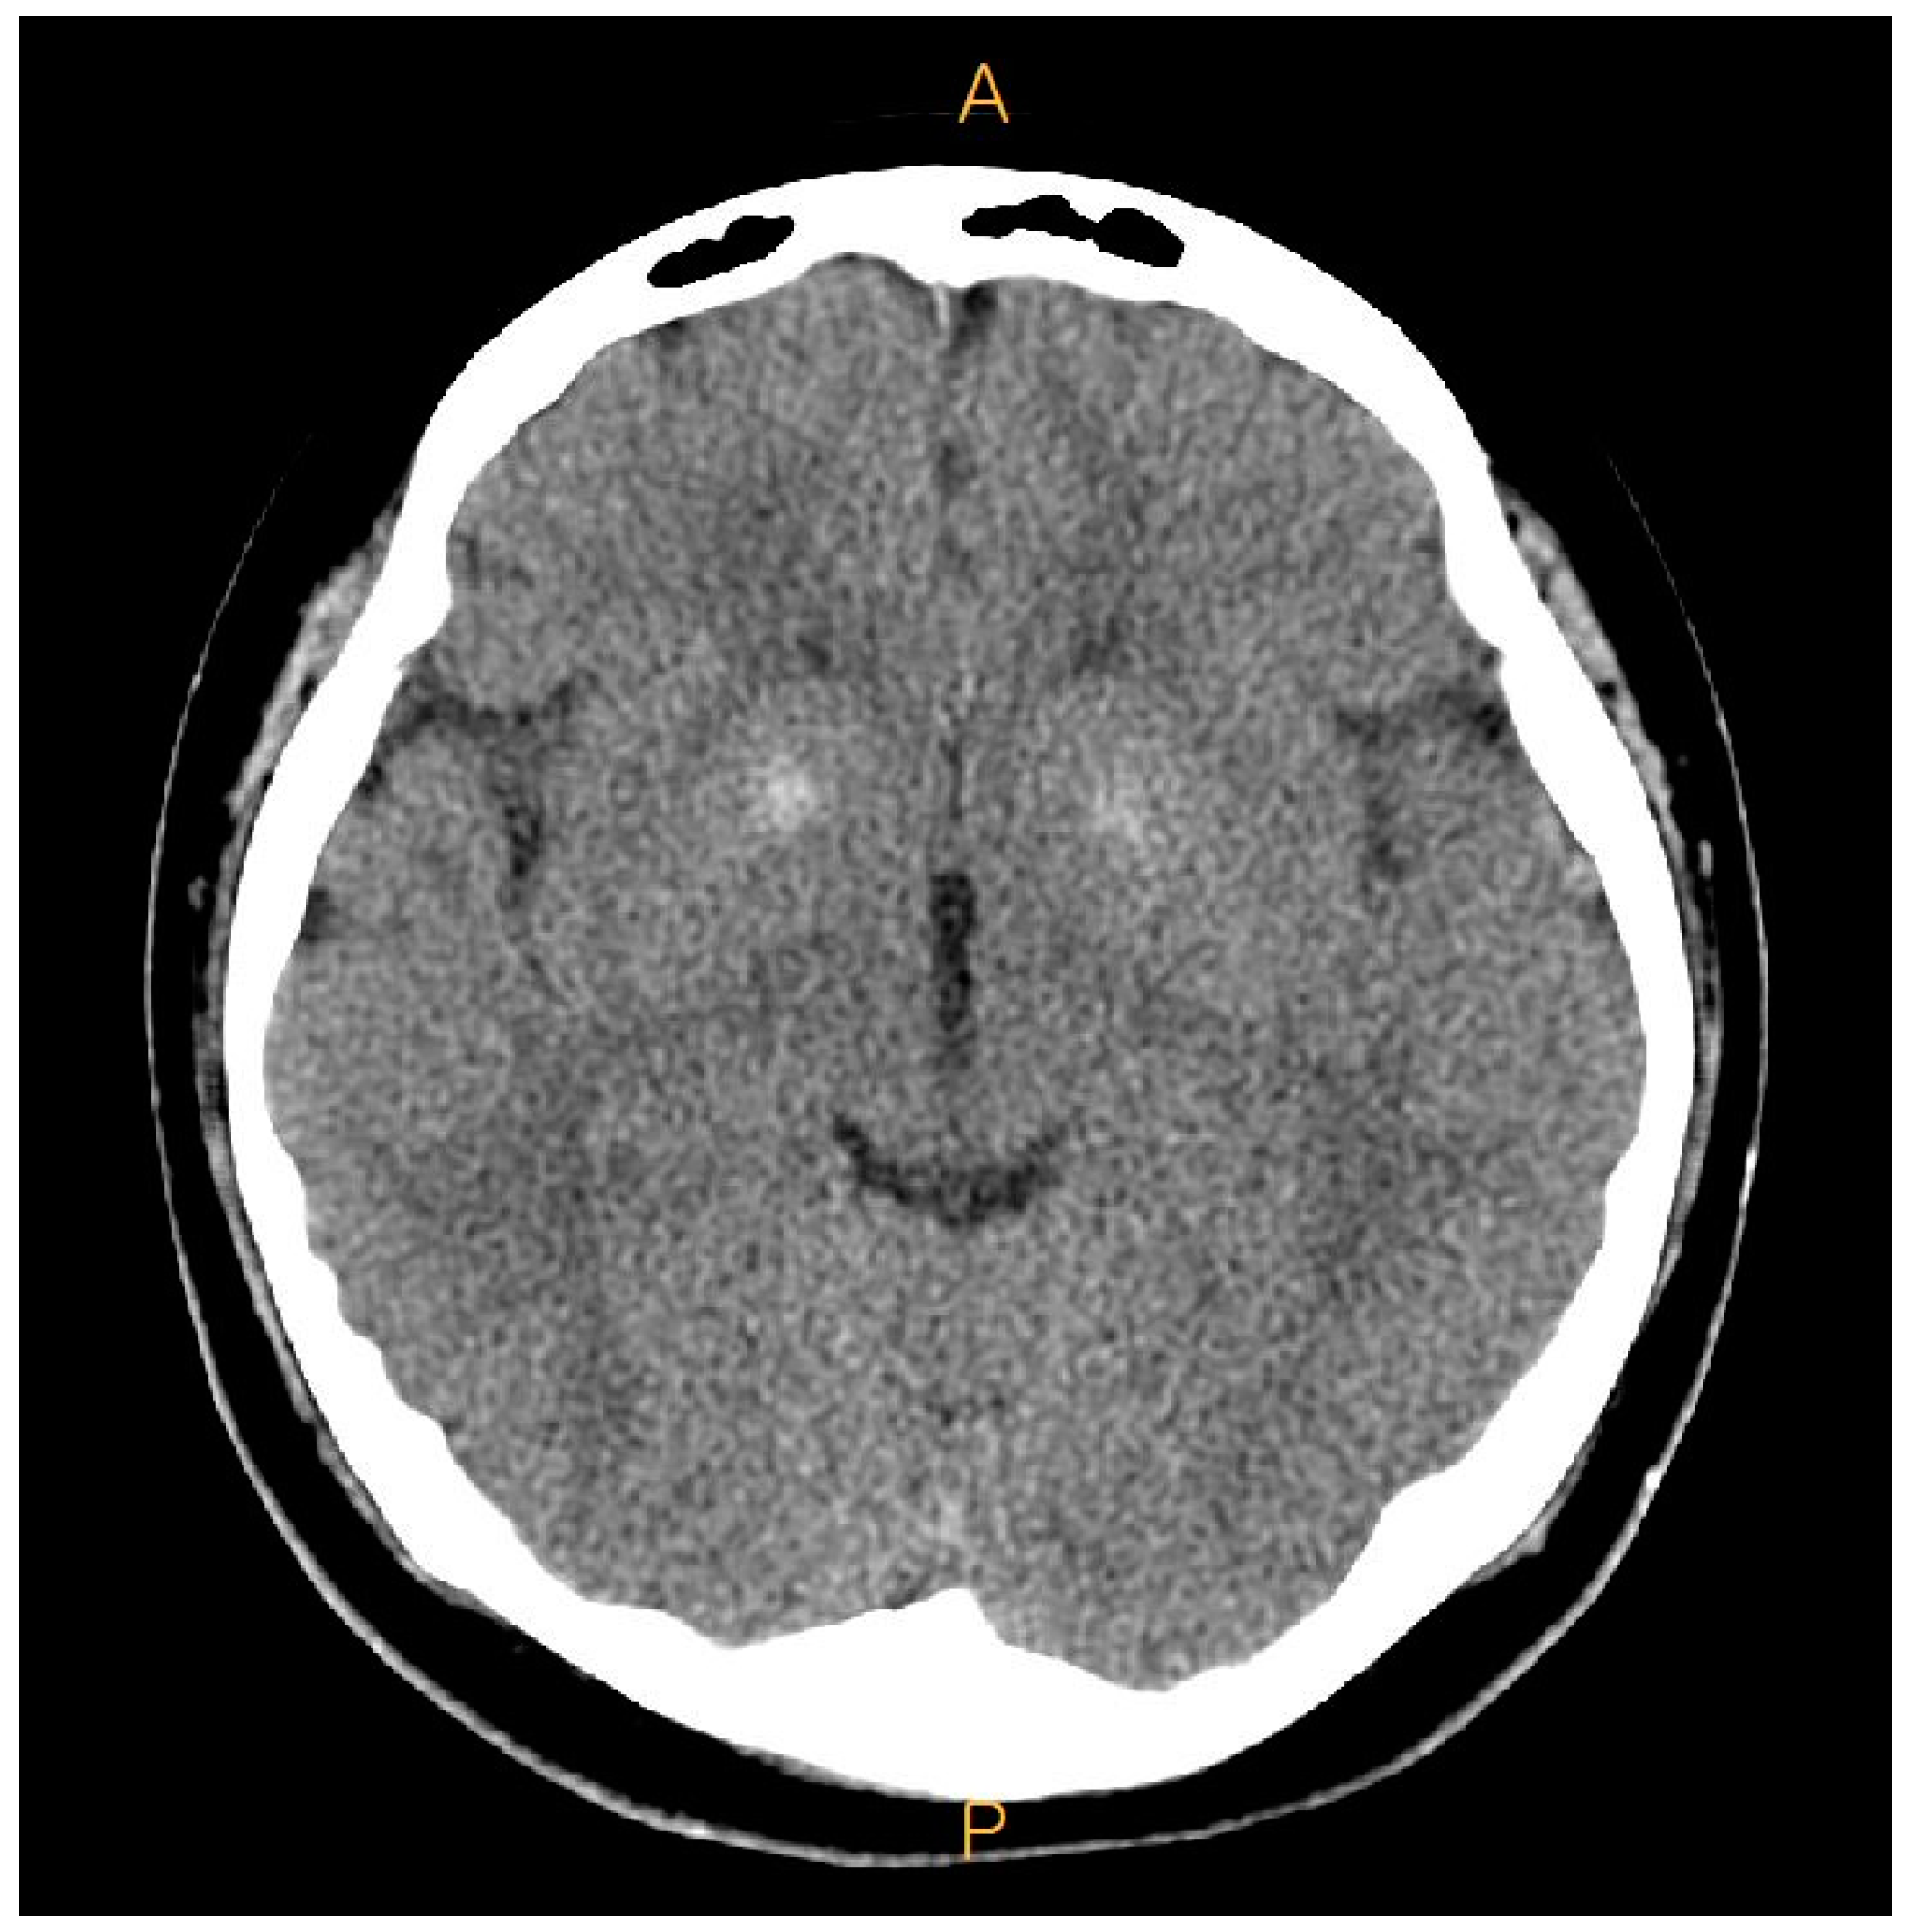

2. Case Presentation

2.1. Preoperative Evaluation

| Brain lesion | O | O | - | - |